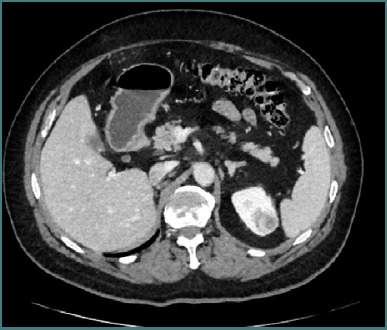

We report the case of a 58-year-old male with metachronous renal tumors and a solitary kidney who had previously undergone an open right radical nephrectomy with extended lymphadenectomy for an invasive renal cell carcinoma (RCC) (pT3a N0M0) in November 2013. In May 2022, during routine surveillance, a left lower pole lesion measuring 2.5 × 2 × 1.6 cm was detected, and the patient was submitted to robot-assisted partial nephrectomy (RAPN). The histopathological study confirmed the presence of a pT1a Fuhrman grade 3 clear cell renal carcinoma. In October 2024, follow-up imaging revealed a new upper pole lesion measuring 4 × 3 × 2.3 cm in the left kidney. The patient was submitted to a novel robot-assisted partial nephrectomy, which was successfully completed using selective clamping of the renal artery. The clamping time was 28 minutes (versus 17 minutes during the initial procedure), and the estimated blood loss increased to approximately 300 mL compared to about 100 mL previously, with a console time of 98 minutes. The patient was discharged after the second surgery in good functional status. The final pathology revealed clear cell RCC, Fuhrman grade 2/nucleolar grade 2 (WHO/ISUP 2016), and pT1a, with negative margins. Despite increased technical challenges during reoperation, postoperative renal function remained stable, underscoring the feasibility of repeat RAPN in a solitary kidney.

Abstract Image